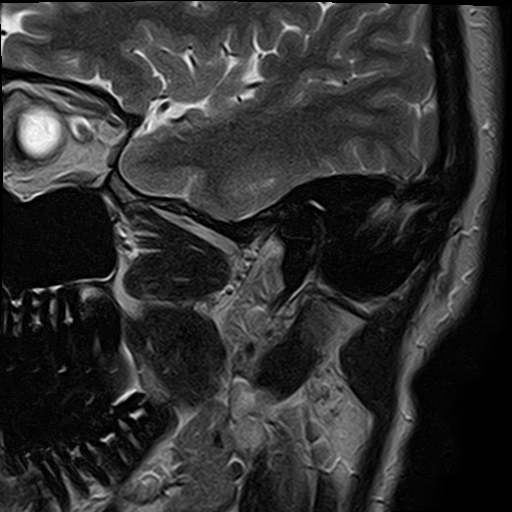

Височно-нижнечелюстной сустав является парным комбинированным суставом и имеет сложное строение. В него входят суставные ямки височной кости, суставные головки нижней челюсти и расположенные между ними хрящевые пластинки – мениски, выполняющие роль амортизаторов.

Чаще всего дисфункция височно-нижнечелюстного сустава обусловлена внутренним повреждением, смещением мениска и суставной головки нижней челюсти. Для определения степени смещения внутрисуставных структур выполняется функциональная проба с проведением МРТ в двух положениях:

Магнитно-резонансная томография является наиболее точным и эффективным методом диагностики поражения височно-нижнечелюстных суставов, так как позволяет получить детальную информацию о состоянии не только костей, но и связочного аппарата, хрящей, менисков, жевательных мышц, окружающих мягких тканей.

В клинике «Доступная медицина» можно пройти исследование МРТ височно-нижнечелюстного сустава на высокотехнологичном оборудовании. Клиника располагает новейшим томографом экспертного класса TOSHIBA VANTAGE TITAN 1,5 Тесла, который благодаря высокой индукции магнитного поля позволяет получать изображения исследуемой зоны в мельчайших подробностях. Томограф производит послойное сканирование области сустава и околосуставных мягких тканей, затем с помощью цифровых приложений преобразует полученные данные в трехмерные изображения превосходного качества.

При проведении магнитно-резонансной томографии на изображениях визуализируются: височная кость, головка мыщелкового отростка нижней челюсти, суставная щель. Помимо костных структур МРТ позволяет оценить состояние мягких тканей – внутрисуставного диска и связочного аппарата височно-нижнечелюстного сустава, жевательных мышц.